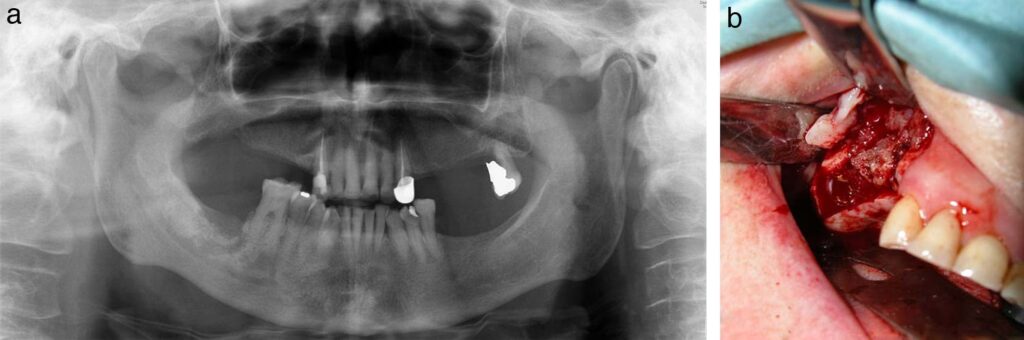

- Ortopantomografía: Útil en estadios avanzados, donde puede mostrar áreas radiolúcidas (destrucción ósea) y radioopacas (secuestros óseos). En estadios iniciales, puede no mostrar hallazgos significativos.

- Tomografía Computarizada (TC) y Resonancia Magnética (RM): Estas técnicas de imagen avanzada son más sensibles para el diagnóstico precoz y permiten determinar la extensión real de la necrosis ósea.

- Evitar cirugía extensa: En la medida de lo posible, se deben evitar los procedimientos quirúrgicos dentoalveolares electivos en áreas afectadas por OMRB, ya que pueden empeorar la condición o crear nuevas áreas de hueso necrótico. El desbridamiento amplio del hueso necrótico rara vez lleva a la curación completa y a menudo se limita a eliminar fragmentos óseos sueltos (secuestros).